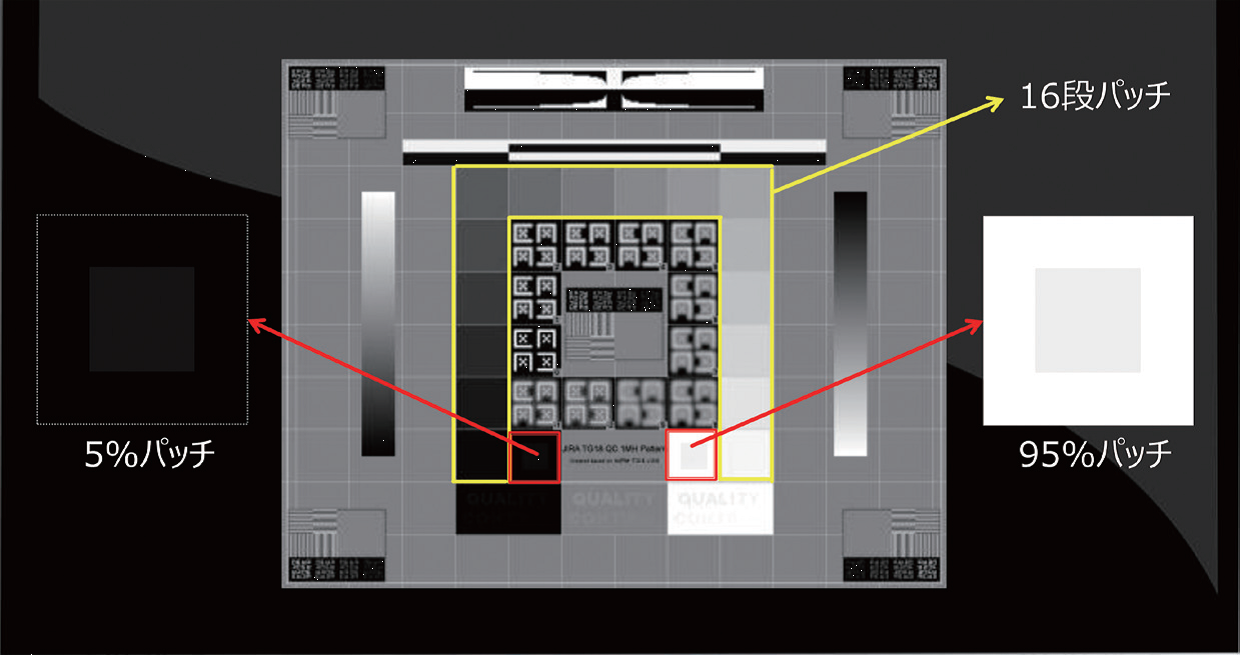

モニタの品質管理の重要性

モニタの日常管理では、まずモニタ画面の清掃・周囲光の確認を行う。続いて全体評価試験で、TG18-QCテストパターンでモニタ全体の画質評価を行う(図1)。次に、各施設で準備した判定用臨床画像で、判定箇所の見え方を確認する。当院では石灰化、スピキュラ、腫瘤の3種類の画像で行っている(図2)。さらに、ファントム撮影で、エックス線発生から画像観察までのシステム全体における画質および線量に関する経時的変化の確認をする。

今回、輝度の変化によって模擬石灰化や模擬腫瘤などの見え方がどのように変化し、それがマンモグラフィのカテゴリー判定にどのような影響を与えるか品質管理用ツールを用いて検証した。検証方法は日常点検と同じ方法で行い、モニタの最高輝度を800カンデラから100カンデラずつ低下させ、それをランダムに表示させて合格基準の判定と見え方の評価を行った。

その結果、輝度の低下によるファントム画像の点数の変化は大きくなかったが、一部の石灰化や腫瘤がぼけて正しく認識できない恐れがあった。また、高輝度領域では白い部分の粒状性が悪くなり、高濃度乳腺で視認性が低下する可能性が考えられた。一部の症例においてはカテゴリー判定を見誤る可能性があるため、モニタ管理の重要性が示唆された。

輝度の低下は、実際の臨床画像や日常点検で気が付くことは難しいが、定量的評価で不変性試験を行うことにより早期発見に繋がるといえる。現状ではモニタの品質管理を行っていない施設も多いが、画像表示モニタの特性を理解し、知識と意識を持つこと、またモニタの品質を管理する技術を身に付けておくことが重要であると考える。